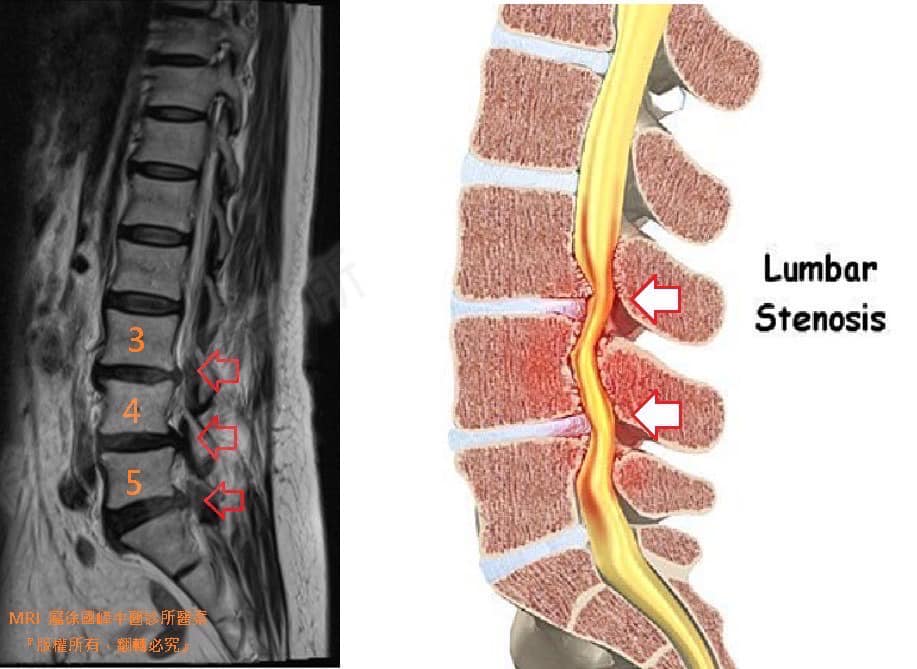

👨⚕️徐醫師從MRI上來看,椎管明顯卡三節所以才導致曾阿姨往前彎腰都會這麼不舒服,歷經2個月的治療,之前腰連臀部至大腿、膝蓋、小腿及左腳底的麻痛都少非常多,跟之前比起來簡直是天差地

2.L3L4;L4L5 第2級椎孔狹窄